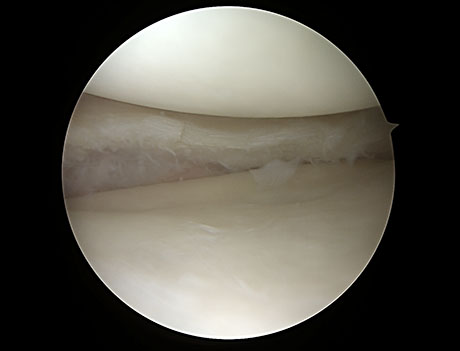

Imagen: se aprecia un menisco sano visto con artroscopia.